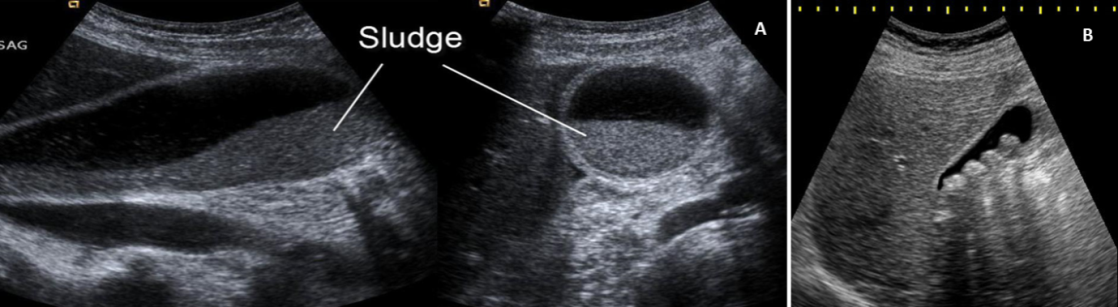

Mixed gallstones are the commonest stones in adults, and the pigment stones are more common in children. Cholesterol supersaturation of bile together with biliary stasis predisposes to cholesterol gallstone formation. Pigmented stones formed due to supersaturation of bile with calcium bilirubinate as in hemolytic disorders. Biliary sludge composed of mucin; calcium bilirubin and cholesterol crystals commonly associated with sickle-cell disease (fig. 2). The biliary sludge may resolve spontaneously or may progress to gallstone development. Persistent sludge gives rise to biliary complications (such as obstruction or infection). Bilirubin converted in the hepatocytes to bilirubin monoglucuronide or di glucuronide by several classes of the enzyme glucuronosyl transferase.

Fig. 2: (A) Biliary sludge (Source: http://www.radiologytutorials.com), (B) Multiple gallstones (Source: http://www.rcstn.net/marisa.bush)